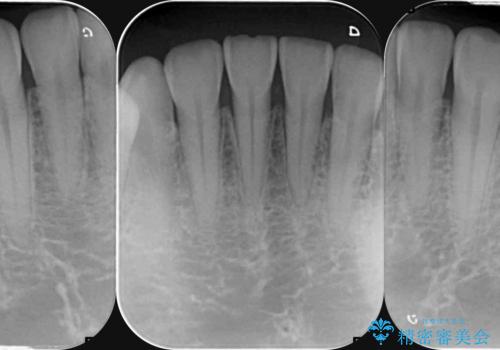

- 歯ぎしり・嘔吐症により歯がすり減ってしまい、色調・見た目を改善したいと来院されました。

神経を温存したまま仮歯に置き換え、噛み合わせの安定を確認したのちに すり減りに強いジルコニアクラウンで最終的な仕上げを行います。

歯の形態・色調を大きく変更する場合ジルコニアクラウンによる治療が耐摩耗性・審美性の観点から推奨されます。